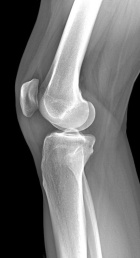

Patient is a 45 y/o Ortho nurse who presented w/ enlarging painful R. knee mass for past year; PMH: ovarian cysts s/p rupture

PE: R. knee w/ well circumscribed mass at the lat. aspect of the patella; + tenderness to palpation; normal PROM; NVI

Zoom image: Radiological image Radiological image.